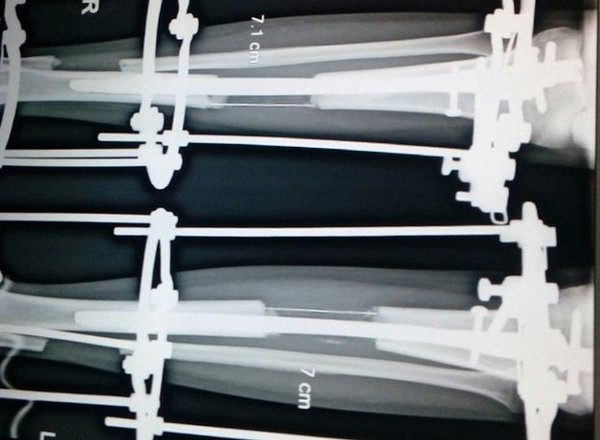

你可能聽過「斷骨增高手術」,醫生會先將病人的骨頭鋸開,然後在腿上裝上輔助工具,等骨頭開始癒合時,伸縮桿就會以漸進的方式拉伸,讓新的骨頭跟組織長出來,整個手術需要約3個月的時間。

這在印度是一項相當普遍的手術,因為價位相較之下低了4-5倍,甚至吸引了許多其他國家的人前往動手術。然而雖然手術普及,但卻沒有相對的保障,德里的沙林醫師 (Amar Sarin) 就表示:「斷骨增高是整型中相當困難的手術之一,但有許多印度醫生只經過1-2個月的實習時間,就因為客源過多而直接替患者進行手術。」患者就像是實驗的白老鼠一樣,結果都是未知數。

不過印度整形外科協會主席卡普爾 (Dr Sudhir Kapoor) 也表示,一般不建議民眾做增高手術,因為很少醫生有相關經驗,再者手術伴隨很高的風險,一不小心就會造成終身跛行,或是其他相關的併發症。